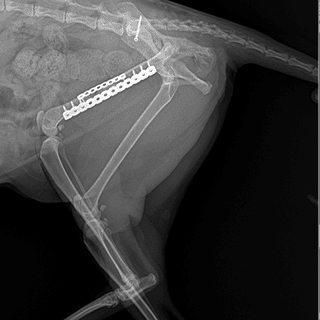

Fracture & Deformity

골절·각기형 센터

정밀한 골절 정복술과 교정으로 안전한 회복을 지원합니다.